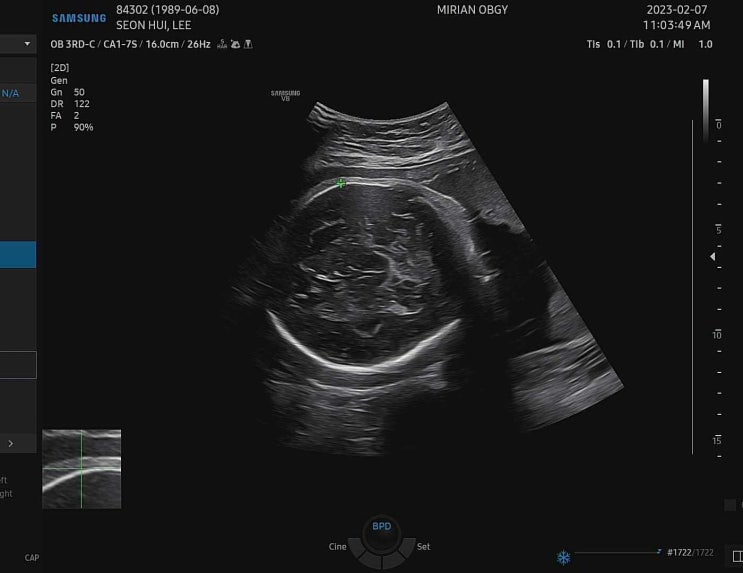

36주 1일 정기검진

이 날은 막달검사 결과 듣고! 다 괜찮은데 다음주 소변검사만 다시 하기로 하고! 초음파로는 아무리봐도 마...